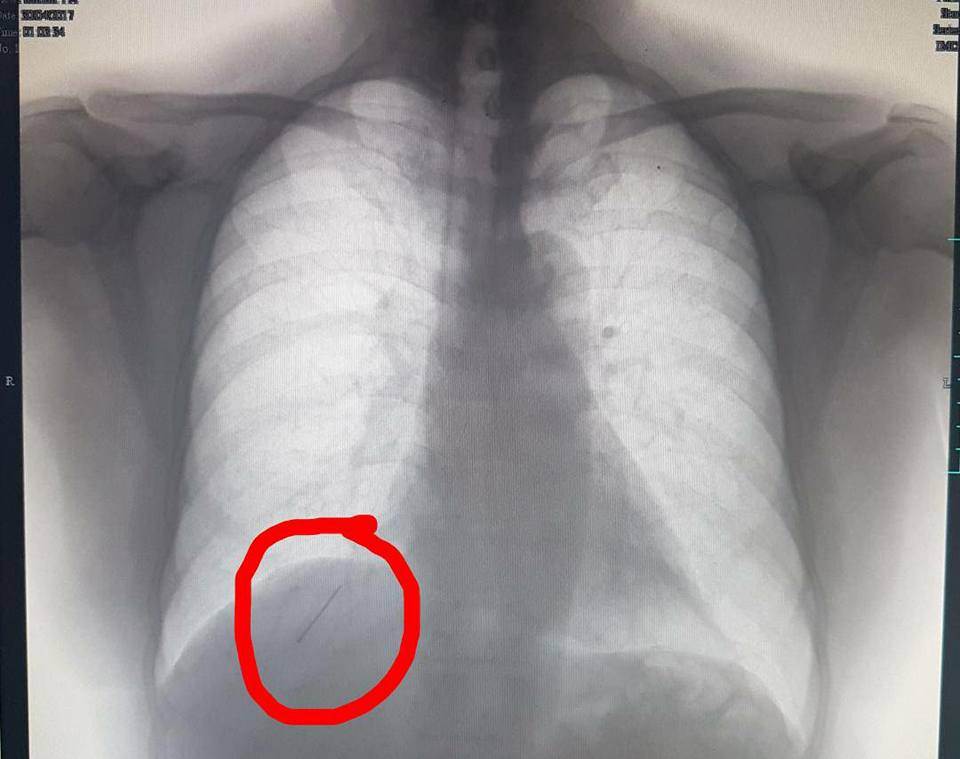

A wedding feast led to several complications for Fr John Thomas who accidentally swallowed a construction pin during the meal. The pin, which had entered the upper part of his right lung, was removed with complex surgical procedures and robotic surgery.

When Fr John Thomas was having his meal at the wedding, little did he know that the sharp object he had swallowed was a pin. He dismissed the pain in his throat and thought it was due to a fish bone. However, eating rice did not reduce pain. After persistence of pain, he sought medical opinion. A few tests and scans found out that he had a pin lodged in the trachea.

This was a weird case of a construction pin which got stuck in the trachea and slipped downwards into the deeper part of the lung on further manipulation, ending up in one of the small airways in the lower lobe of the right lung. Attempts by the ENT to retrieve the pin only pushed it further down the airway. Due to this, there was a severe risk of infection, further migration, and injury to other vital organs. He was originally treated with bronchoscopy. However, due to the precarious position of the pin, bronchoscopic tools were insufficient. He was referred to the cardiothoracic surgery team.

Surgery was combined with simultaneous bronchoscopy and fluoroscopy to localise the pin and remove it successfully. Dr Balasubramaniam K R, Consultant Minimally invasive and Robotic Thoracic surgeon, led the thoracic team in performing the surgery. He stated, “Locating the pin in the small airways in the deepest part of the lung was a big challenge during surgery.”